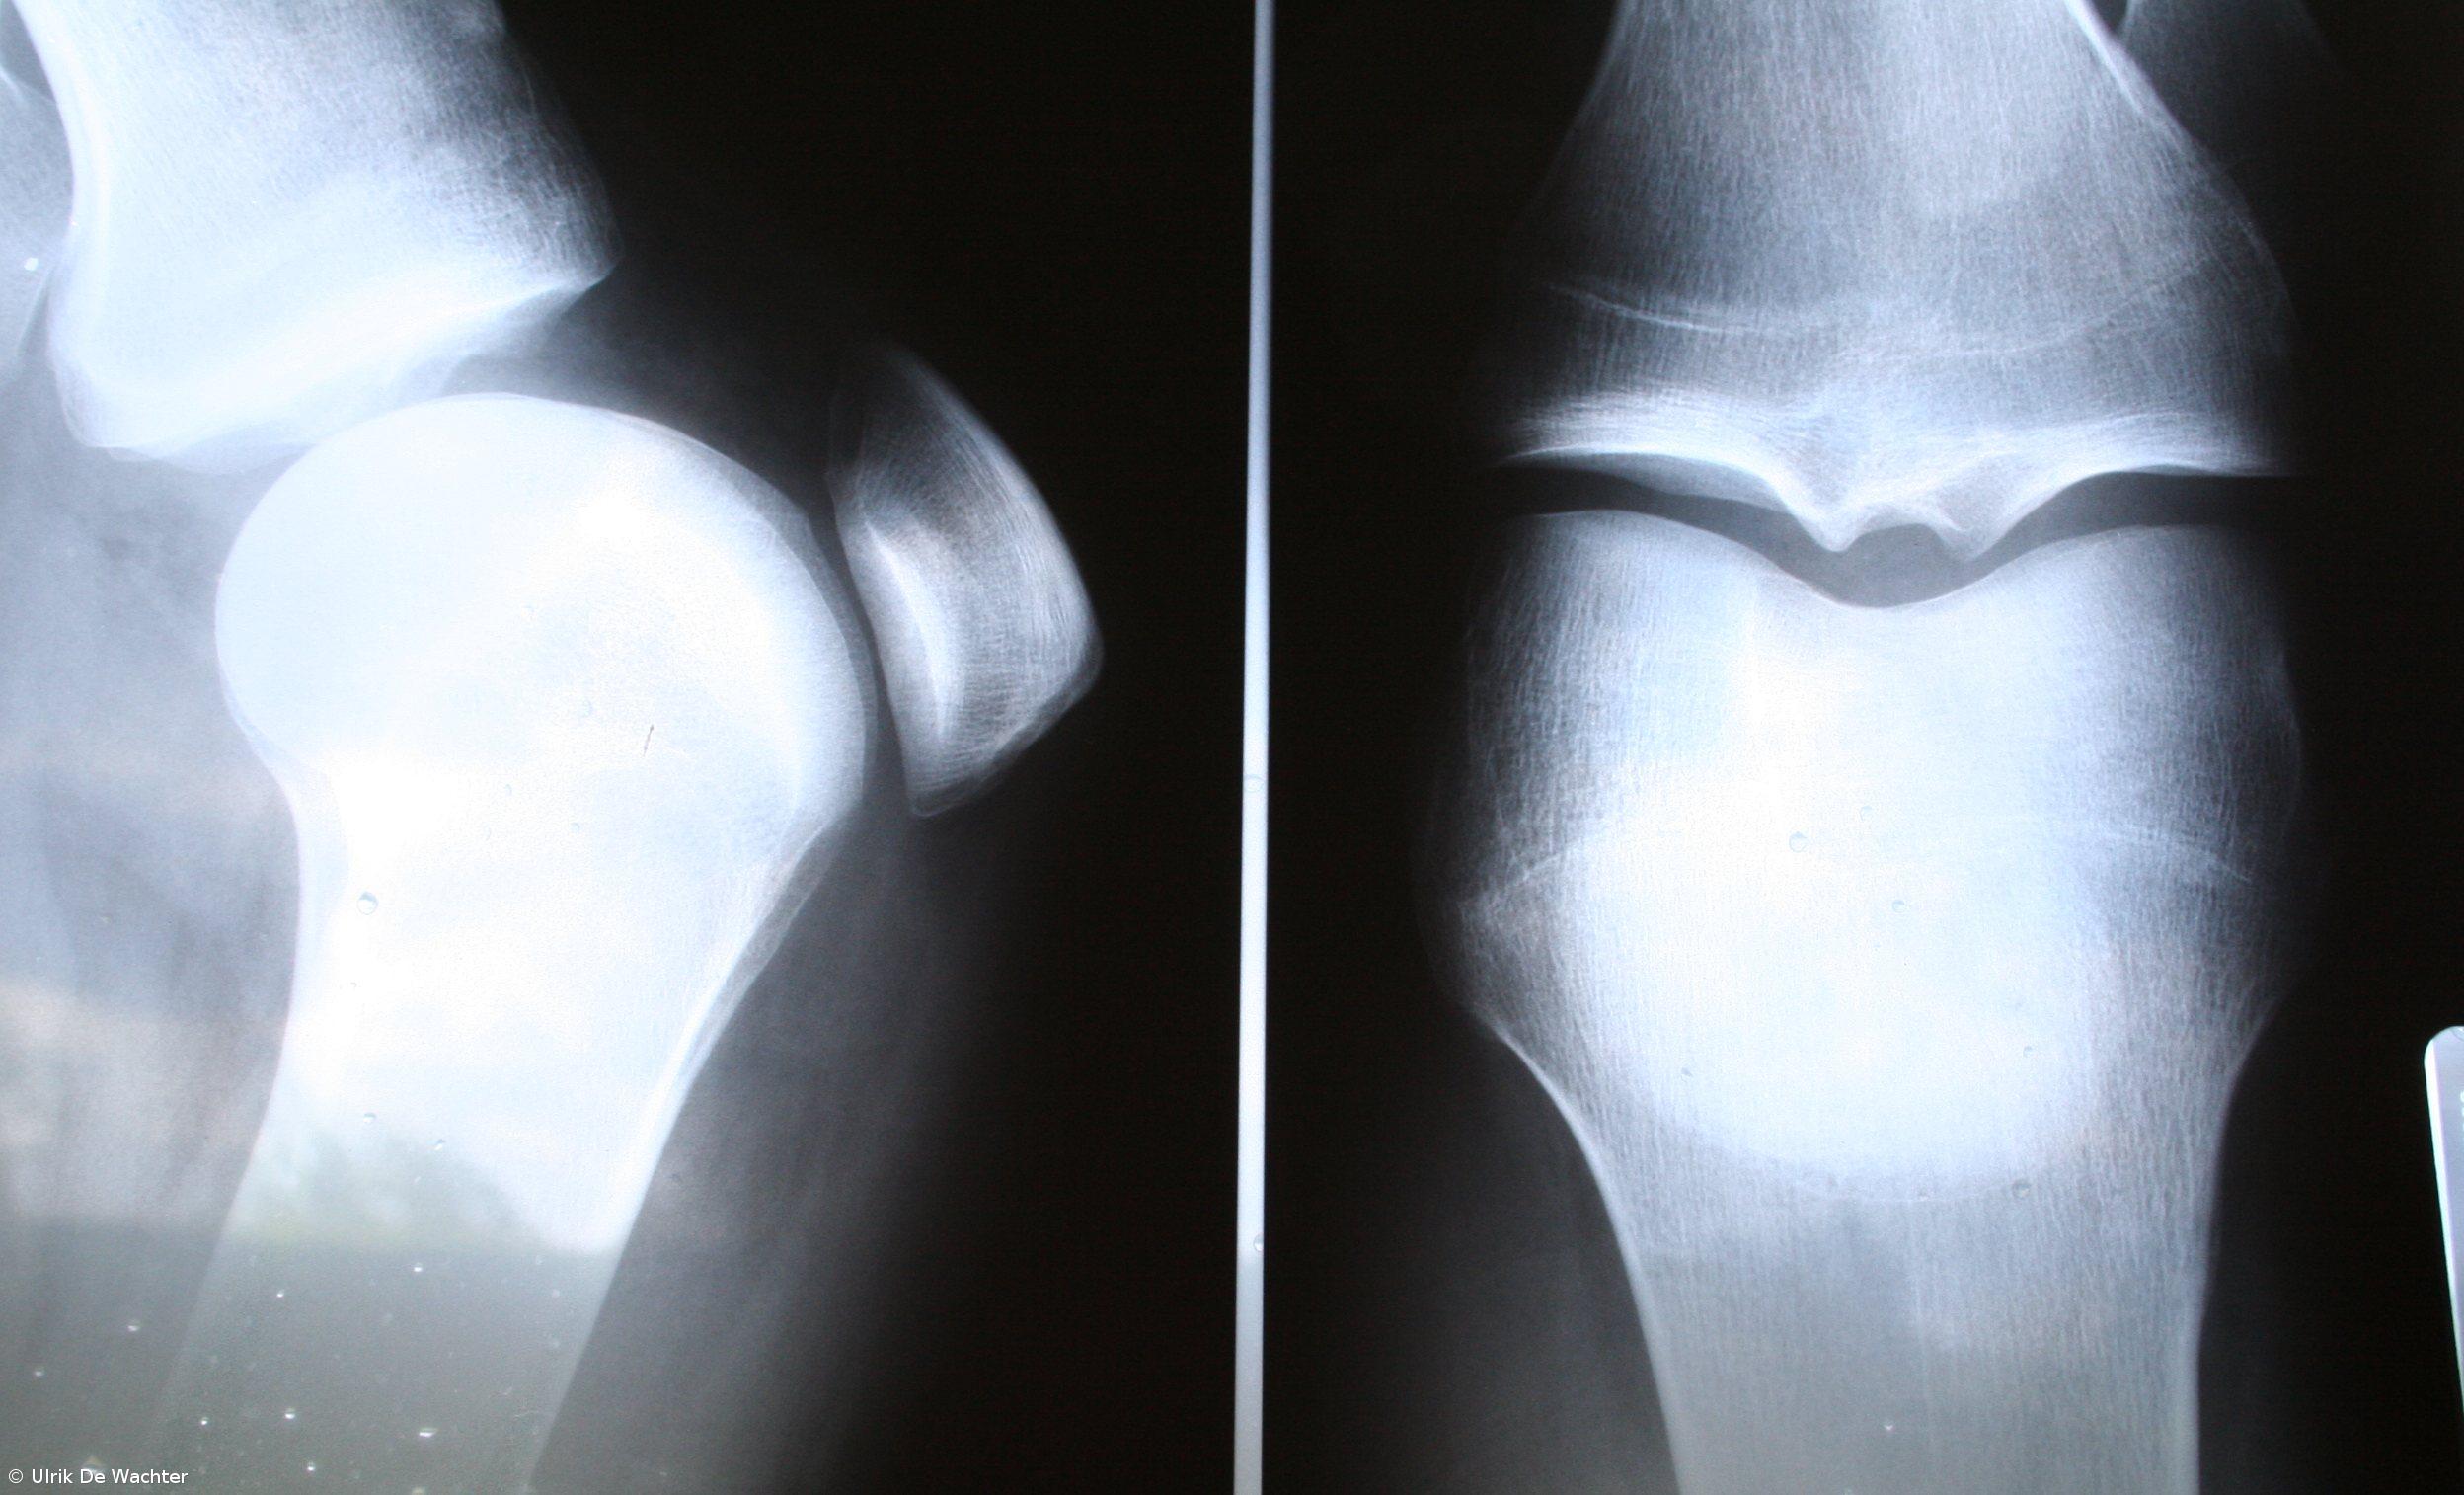

Segundo o presidente da Liga, Jaime Branco, entre as doenças mais frequentes estão a osteoartrose, doenças de coluna, osteoporose, fibromialgia, artrite reumatóide ou tendinites.